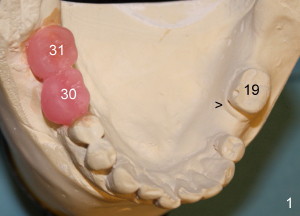

Mr. Lip returns to clinic for #30 and 31 implant placement. At the time of impression, there is no sign of gingival swelling around the tooth #19 (Fig.1: >; although the tooth has suspected root fracture). The patient requests keeping this affected tooth as long as possible while #30,31 implants are being placed and restored. This is not the case at the appointment of implant placement on the other side (Fig.1': *). There is localized gingival erythema and edema at the ML line angle. It appears that the treatment plan should be changed: the number of implants to be placed should be reduced from two to one and the infected tooth should be extracted to decrease the chance of implant infection. These two procedures are intended to be done at the same time so that bone harvested from #30 implant osteotomy (Fig.2) can be saved (Fig.2': < in dapen dish) and grafted in #19 sockets (Fig.3', 4'), particularly in the mesial one with severe bone loss due to root fracture.